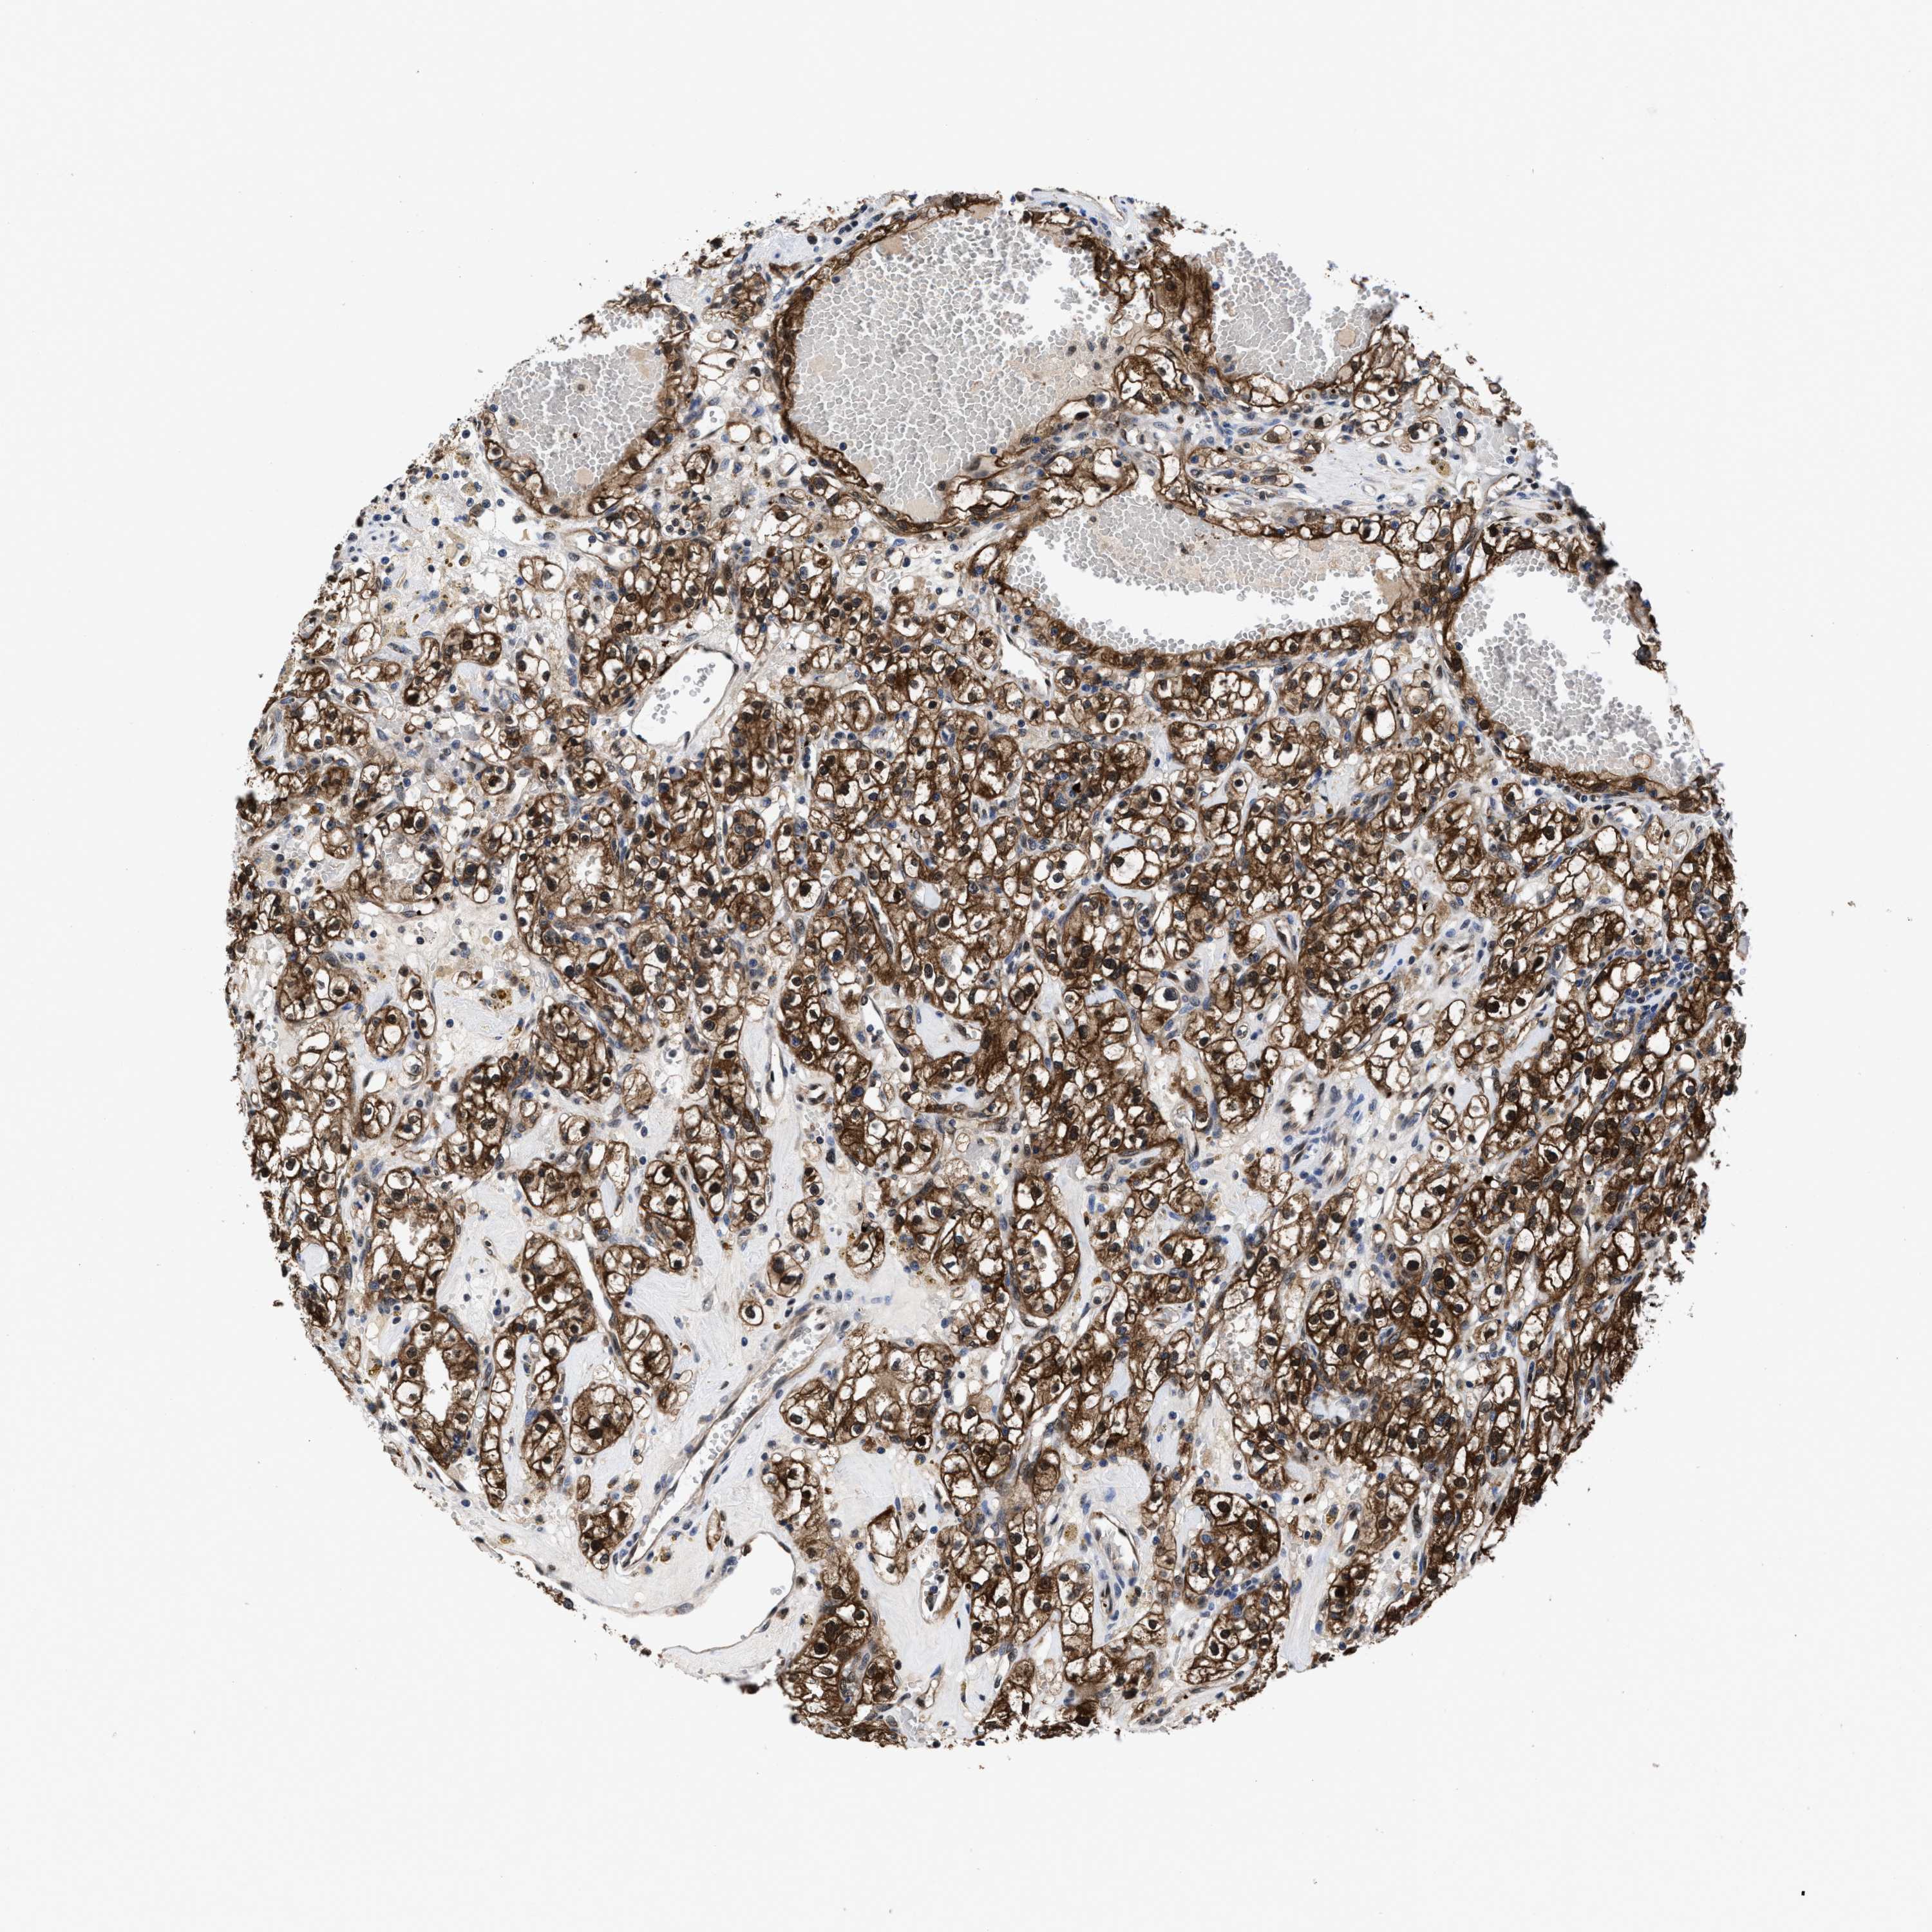

KIDNEY RENAL CLEAR CELL CARCINOMA (VALIDATION) - Interactive survival scatter ploti

ACLY is not prognostic in Kidney Renal Clear Cell Carcinoma (validation)

: 169.05

Average pTPM 211.9

Number of samples 100